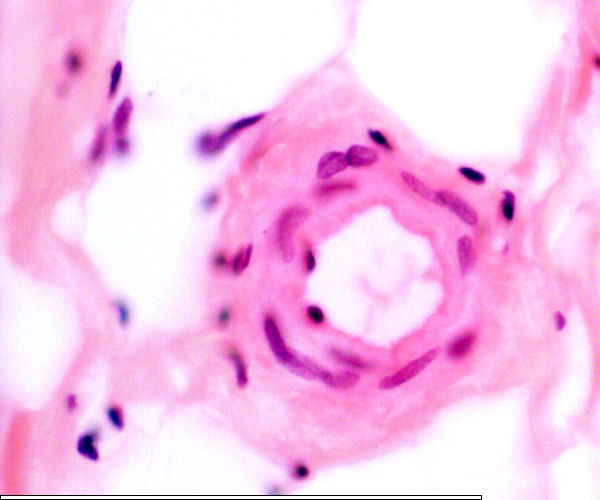

Vasa vasorum